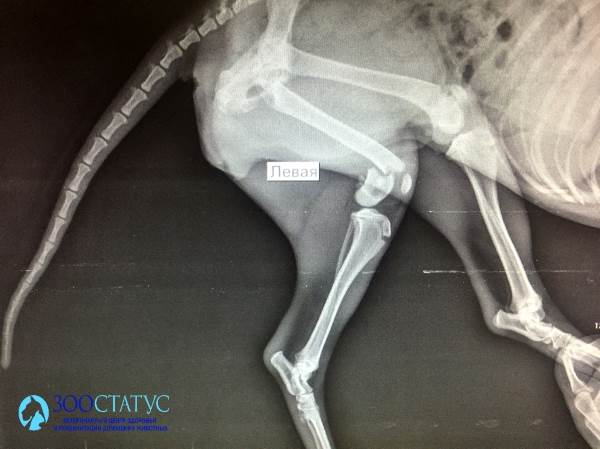

Переломы костей у собак - нередкое последствие различных травм и некоторых патологий (например, вторичного гиперпаратиреоза).

Переломы могут быть открытыми и закрытыми, а также неполными (трещины в кости, сколы).